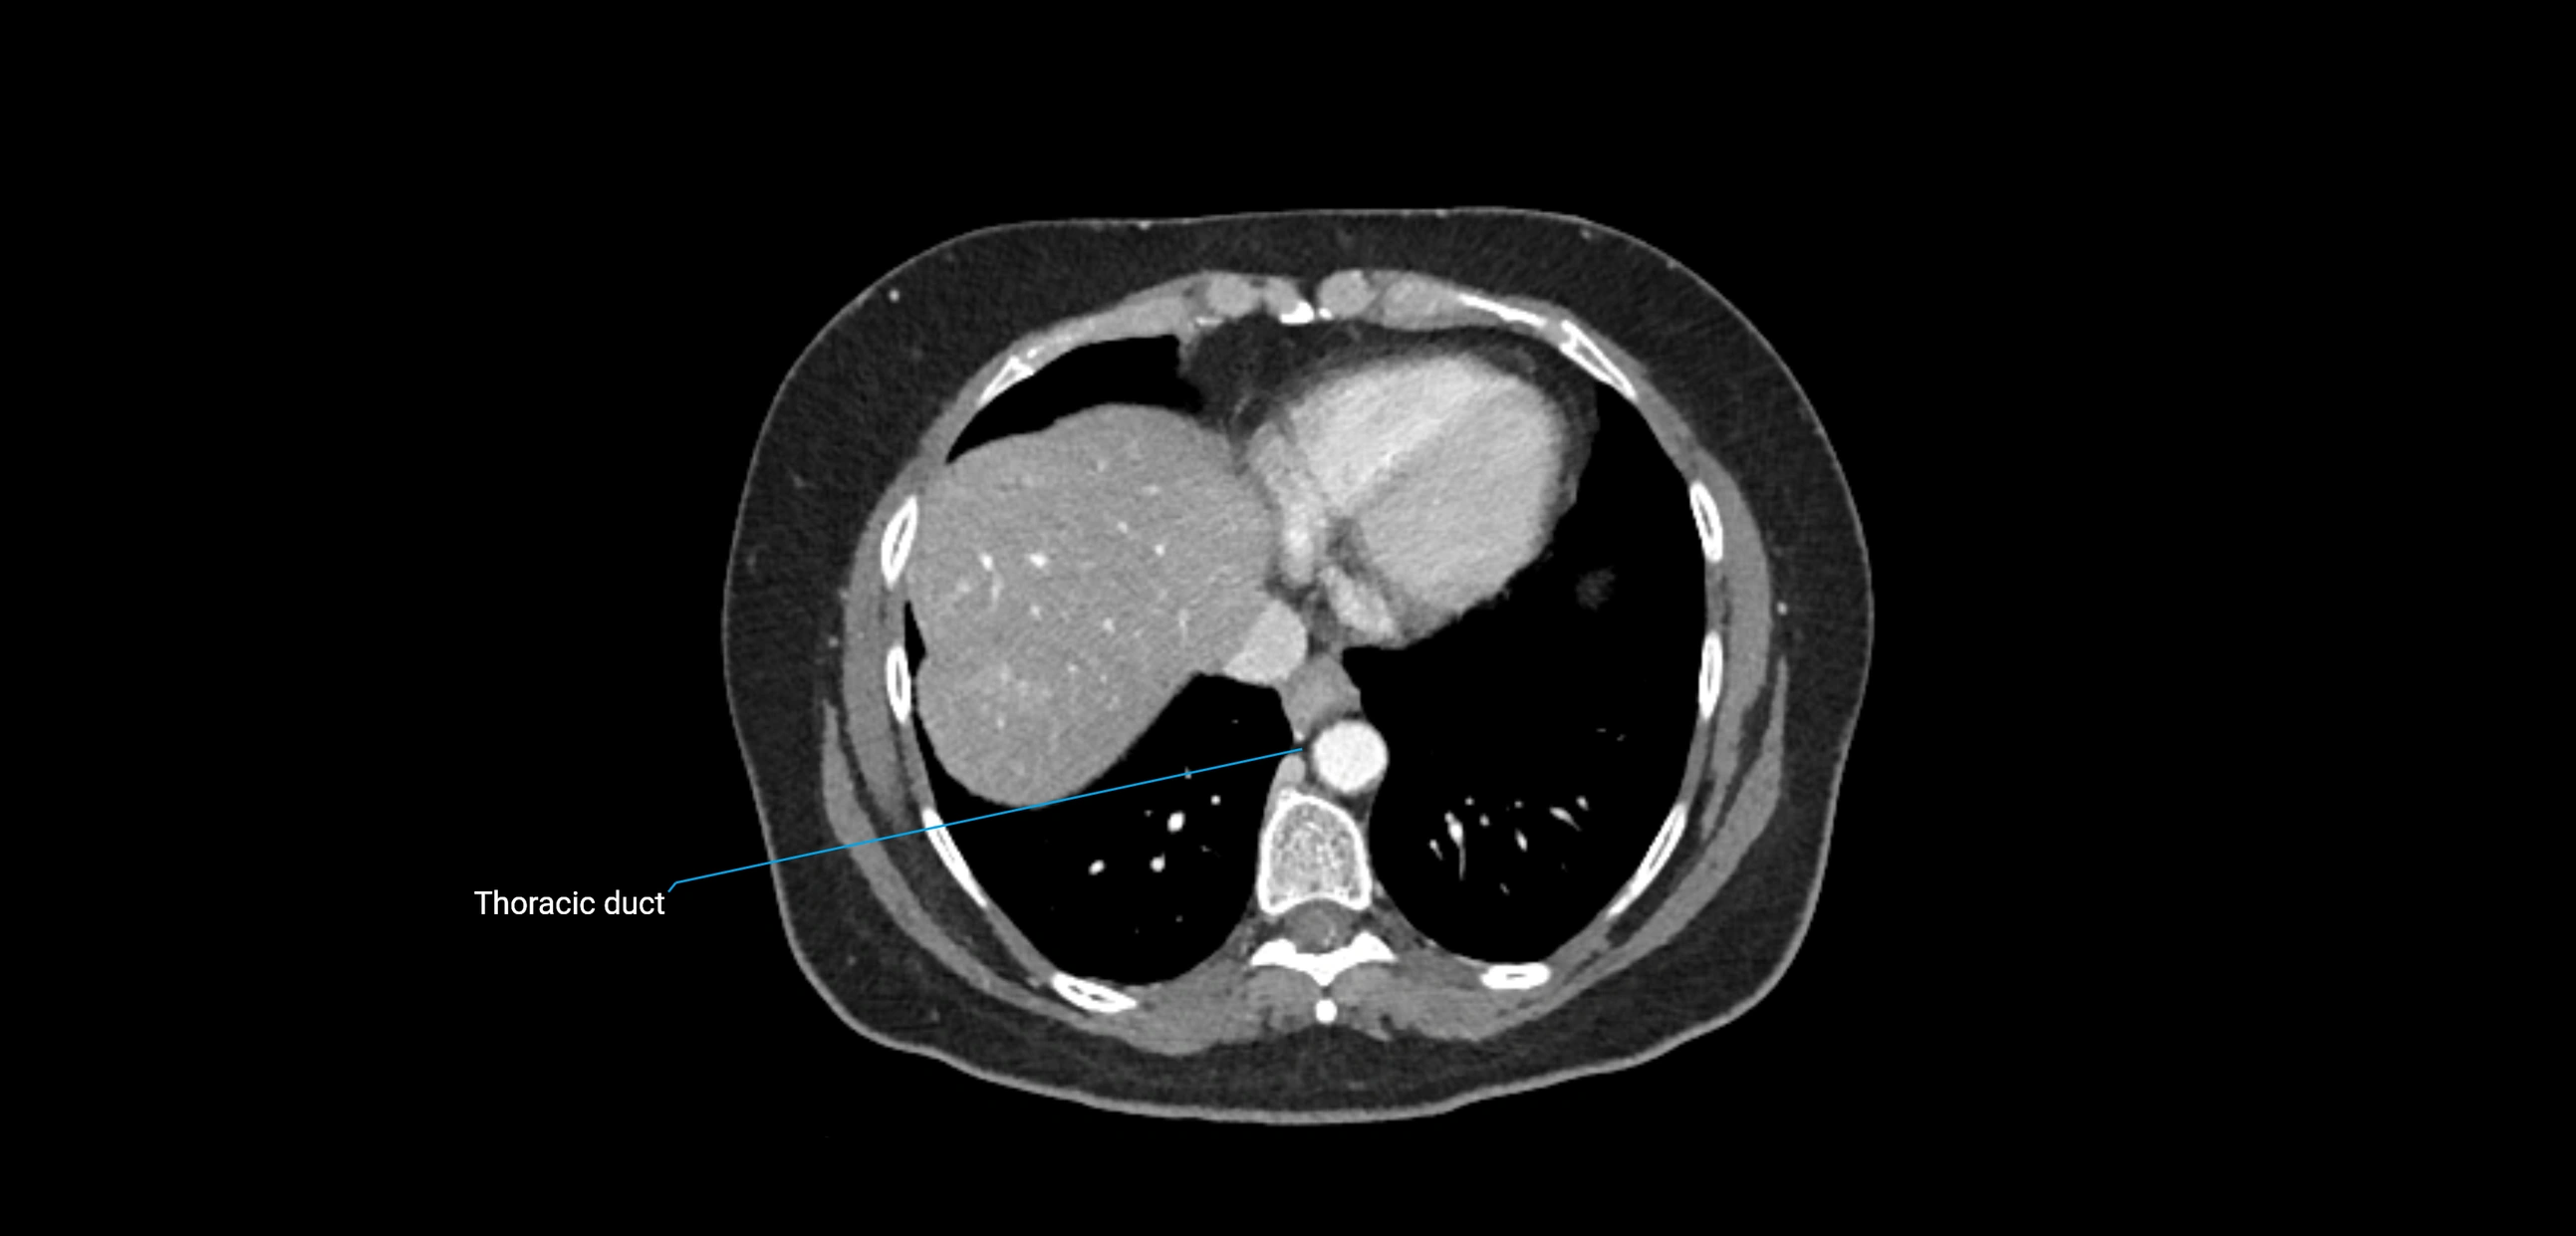

CT Appearance

CT Pre-Contrast:

• Nodes appear as soft-tissue density nodules adjacent to the aorta and IVC

• Calcification may be seen in chronic infections (e.g., tuberculosis)

CT Post-Contrast:

• Normal nodes enhance homogeneously

• Malignant nodes may show heterogeneous enhancement, central necrosis, or conglomerate formation

• Size >1 cm short axis is suspicious, though morphology and distribution are equally important